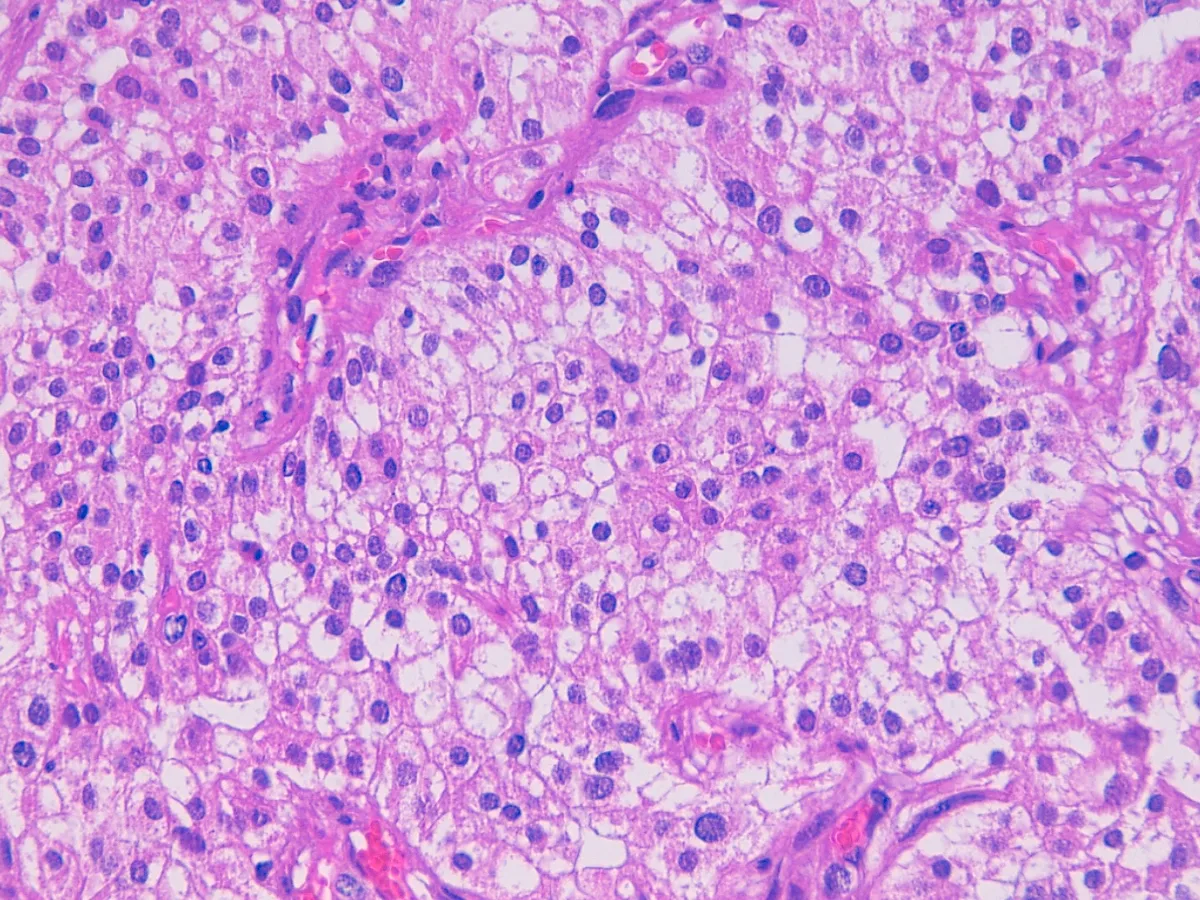

Diagnóstico: MESOTELIOMA EPITELIOIDE DIFUSO PERITONEAL

- La morfología más frecuente es la epitelioide (75%), seguida de la sarcomatoide que confiere peor pronóstico. Las células se disponen formando túbulos, papilas o nidos sólidos (PMID: 15981812).